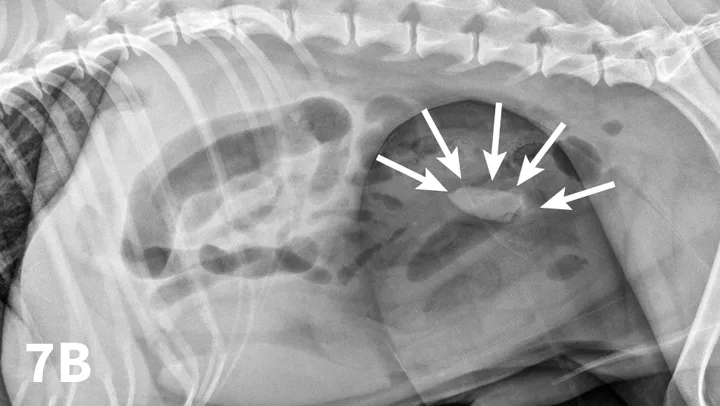

FIGURE 7

Left lateral radiograph of a 9-year-old Jack Russell terrier with a 4-day history of vomiting and anorexia (A). Moderate dilation with small gas bubbles (stars) of the small intestinal tract is noted (B). Left lateral compression radiograph of the same dog. A wooden spoon was used to apply compression to the caudal abdomen. Ventral to the colon, a well-defined ovoid mineral opacity (arrows) is visible within a dilated small intestinal loop. This was a piece of rubber confirmed at surgery.

With the patient in lateral recumbency and using a wooden or plastic spoon or paddle, the abdomen is mildly compressed in an area of concern identified on survey films (Figure 7A). Using the paddle and compression, adjacent bowel or masses are displaced to increase radiographic conspicuity. This results in better visualization of potential foreign material (Figure 7B), plication of small intestinal loops in cases of linear FBs, or intestinal masses otherwise obscured by superimposed bowel.